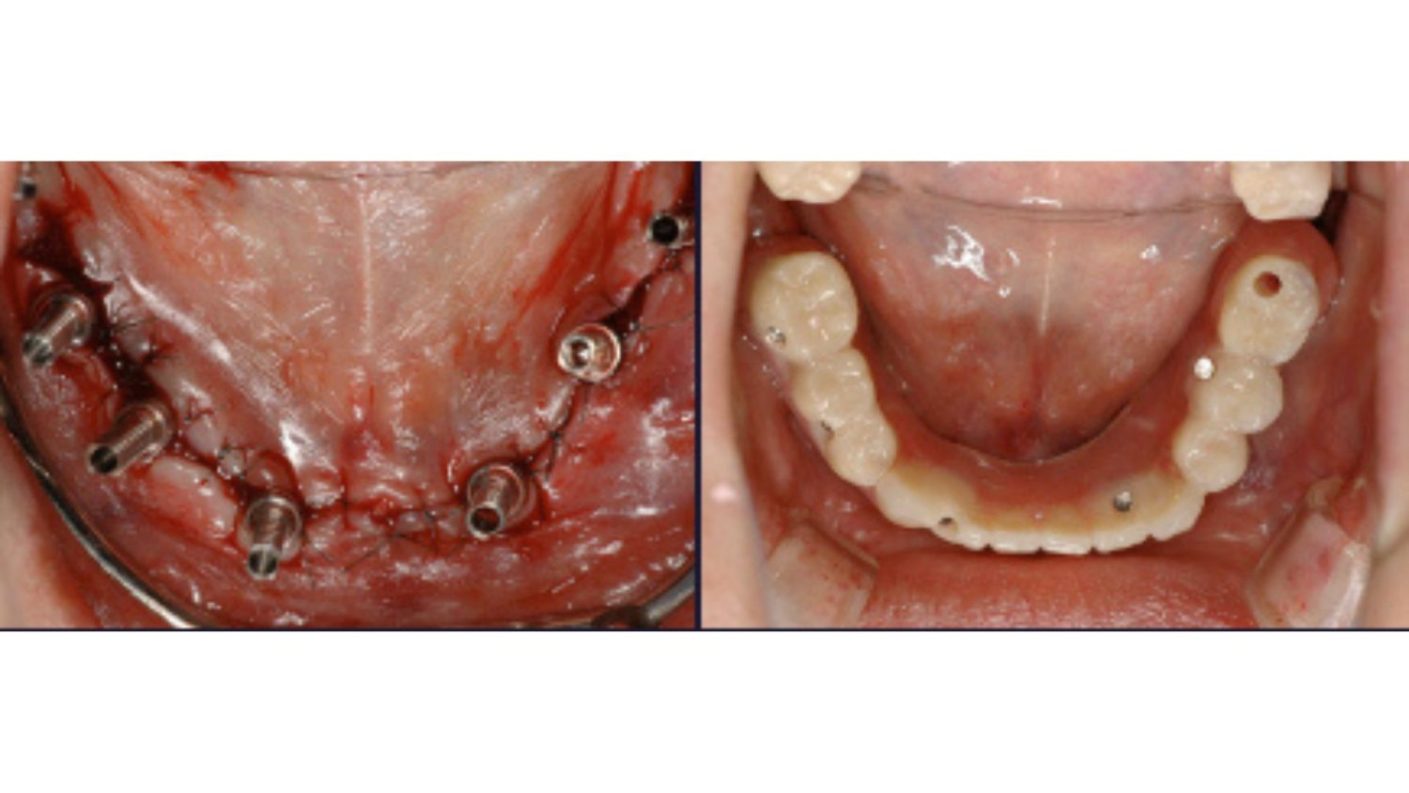

多数歯欠損のインプラント治療の症例(うえだ歯科)

| 主訴 | 歯がグラグラで噛むことができない。インプラントをして欲しい。 |

| 治療内容 | 歯周病で骨の吸収が重度で保存不能なため抜歯、仮の入れ歯を作り、6ヶ月の抜歯窩の治療の後に、インプラントのCTによる診査診断を行い、下顎に6本インプラント埋入と同時に仮歯を入れる。その後、上顎は8本のインプラント埋入と同時に仮歯を入れる。左右上6はソケットリフトによる上顎洞拳上術を行う。その後免荷期間6ヶ月待ってセラミックを用いた上部構造作製、装着しメンテナンスに移行する。 |

| 治療費 | 9,000,000円(税込) |

| 治療期間 | 2年3ヶ月 |

| 治療回数 | 90回 |

| 想定されたリスク | 重度の歯周病により無歯顎になったため、プラークコントロール不良による、術後のインプラント周囲炎が懸念される。歯冠の部分はセラミックなため欠ける可能性がある。 |